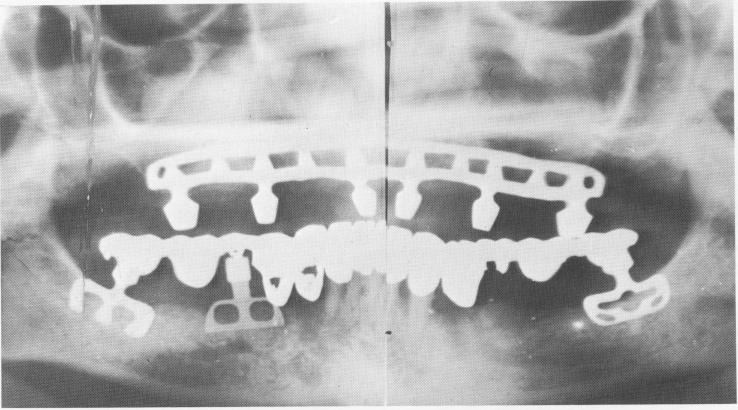

Fig. 11-176. A Panorex of the completed maxillary restoration. The mandibular restoration had been successfully functioning for over a year. Since it was one of the earlier cases the prosthesis was prefabricated before the implants were set into the bone. Large holes were made inside the pontics corresponding to the implants and then they were locked to the protruding posts with acrylic resin, which cannot be seen on a radiograph. This method is no longer done since the blades can remain unsupported for many weeks after their initial insertion. (From Linkow, L. I.: Status of oral implants, 1969, Inform. Odontostomat., Vol. 1, 1969.)

1 Panorex of completed maxillary restoration